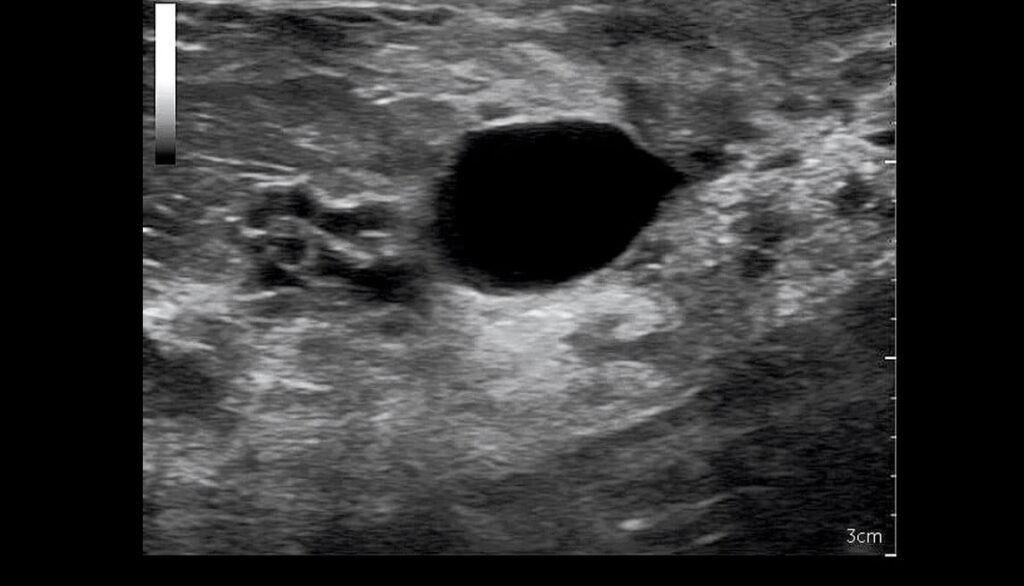

O BI-RADS® ultrassonográfico utiliza uma graduação em categorias idêntica à do BI-RADS® radiológico. Isto é uma vantagem, no sentido de que a comunidade médica envolvida em diagnóstico mamário já está acostumada a raciocinar dentro das faixas de risco estabelecidas pelo BI-RADS® radiológico.

A classificação dos achados ultrassonográficos se enriqueceu, definindo apropriadamente as lesões de ecogenicidade complexa, os cistos complicados, a orientação da lesão, o halo ecogênico, a presença de achados associados.

O BI-RADS® ultrassonográfico trouxe, ainda, uma classificação da ecotextura de base da mama inédita, incluindo três categorias: mamas homogeneamente gordurosas, mamas homogeneamente fibroglandulares e mamas heterogêneas. A razão dessa classificação vem do fato de que determinados tipos de ecotextura de base poderiam favorecer, enquanto outros poderiam diminuir a sensibilidade da ultra-sonografia mamária.